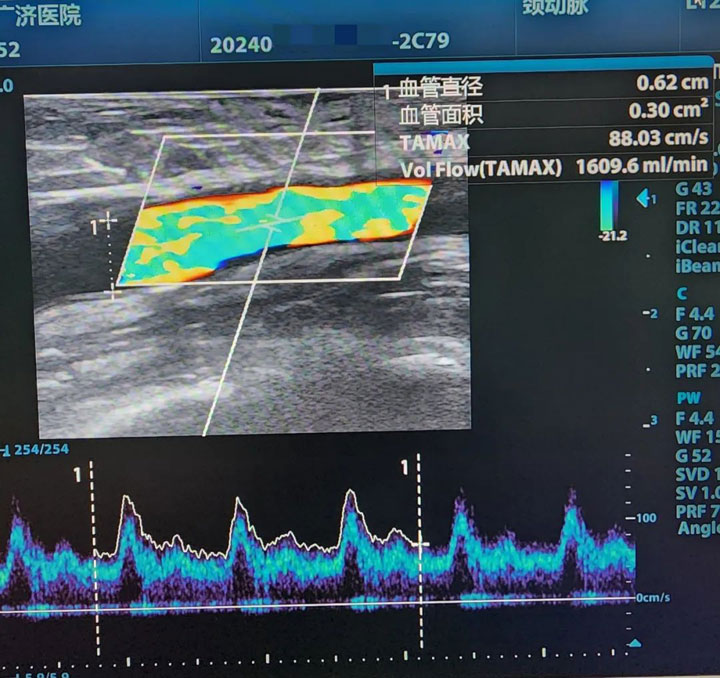

▲再通后

作为一名专业的透析通路医生,魏然主任首先为其详细评估两侧动静脉内瘘,彩超探查,右前臂动静脉内瘘大量血栓形成,左前臂动静脉内瘘血栓形成。急查双上肢动、静脉+多普勒血流图:右侧动静脉内瘘吻合口至头静脉弓锁骨下静脉汇入点处全段血栓形成。左侧桡动脉闭塞,左侧前臂头静脉血栓形成。

“左侧老瘘前臂桡动脉、头静脉血栓,右侧新瘘血栓形成距离更长,贵要静脉、上臂头静脉、锁骨下静脉都不乐观。”考虑到患者远期通畅率及经济压力等问题,魏然主任为患者制定了两套手术方案,首选打通左前臂血栓闭塞2年的“老瘘”。完善术前准备后,魏主任第一时间安排手术,在无影灯下,他手持超声探头,熟练操作,一点一点清除血栓开通闭塞,终于闭塞2年之久的内瘘再通了。“虽然难度大,但是手术顺利,放心吧。”

术后1个月随访,老人再通的内瘘功能恢复良好,使用通畅。为了表达对医生妙手仁术的感谢,家属送上订制的锦旗。“我知道你们不收红包,锦旗一定要收下,这是我们全家人的心意。如果不是魏主任,我们只能带着他去外地再试试了,谢谢您,救了我的父亲,帮了我们全家。谢谢您。”